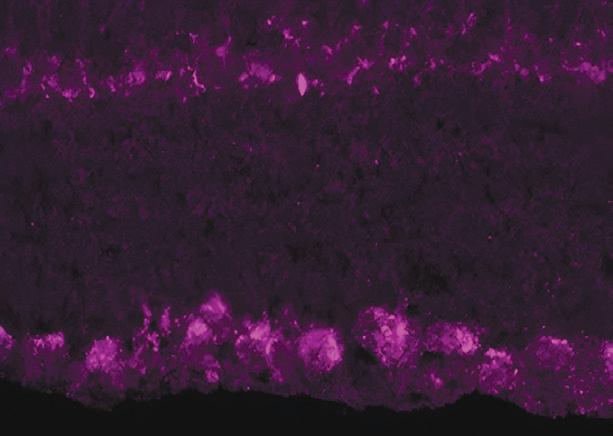

Neuroprotection-Based Therapies: Expanding Team

Crandall Center Associate Director David Krizaj, PhD, and research collaborators from the University of Utah Department of Chemistry and College of Pharmacy are in the final stretch of experiments for a powerful new therapy to lower pressure associated with glaucoma and prevent optic nerve cells from dying—a function known as neuroprotection. Backed by a venture capital funder, he is conducting clinical studies as the last step before applying to the FDA to test in humans.

The initiative grew in January as neuroscience researcher Zachary Davis, PhD, joined the Moran Eye Center. Working with Alessandra Angelucci, MD, PhD, his lab is assisting in Crandall Center efforts to develop glaucoma disease models and techniques for studying the impact of glaucoma on visual perception in the brain.

Another Moran collaborator, Frans Vinberg, PhD, plans to conduct testing on functioning human photoreceptor cells to study signaling when the cells are exposed to pressure.

Microscopy and color labeling of retinal ganglion cells (RGCs), the cells that form the optic nerve and are damaged by glaucoma. Courtesy of Krizaj Laboratory members Monika Lakk, PhD, and Chris Rudzitis.